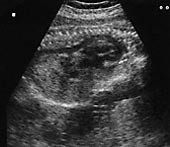

Blodtrykket ved innkomst var 140/90 mm Hg, urinen gav svakt utslag på protein (dipstiks 1+), hemoglobinverdien var 10,5 g/ 100 ml, MCV 73 fl (referanseområde 80 – 99 fl), trombocytter 252 × 109/l (referanseområde 150 – 450 × 109/l), CRP< 10 mg/l (referanseområde< 10 mg/l), ASAT 129 U/l (referanseområde 10 – 35 U/l), ALAT 151 U/l (referanseområde 10 – 35 U/l), LD 775 U/l (referanseområde< 425 U/l), kreatinin 81 µ mol/l (referanseområde 60 – 125  µ mol/l) og urinsyre 440  µ mol/l (referanseområde 120 – 480  µ mol/l). Ultralydundersøkelse viste ascites og ødem hos fosteret (fig 1). Hjertet var forstørret, det var lite fostervann og placenta var stor.

Etter enda ett år var kvinnen gravid på ny. Barnefaren var den samme. Hun ble henvist til Kvinneklinikken i svangerskapsuke 35 fordi fosteret var veksthemmet. Hun var i god allmenntilstand og hadde ikke tegn til preeklampsi. Hemoglobinverdien var 9,4 g/100 ml. Ultralydundersøkelse viste et veksthemmet foster ( −  25 %), lite fostervann og forstørret placenta. Fosterhjertet hadde fortykkede vegger og fylte ut nesten hele thorax, både aorta (fig 2) og navlevenen virket utvidet. Leveren var stor, men fosteret hadde ikke ascites eller pleuravæske.